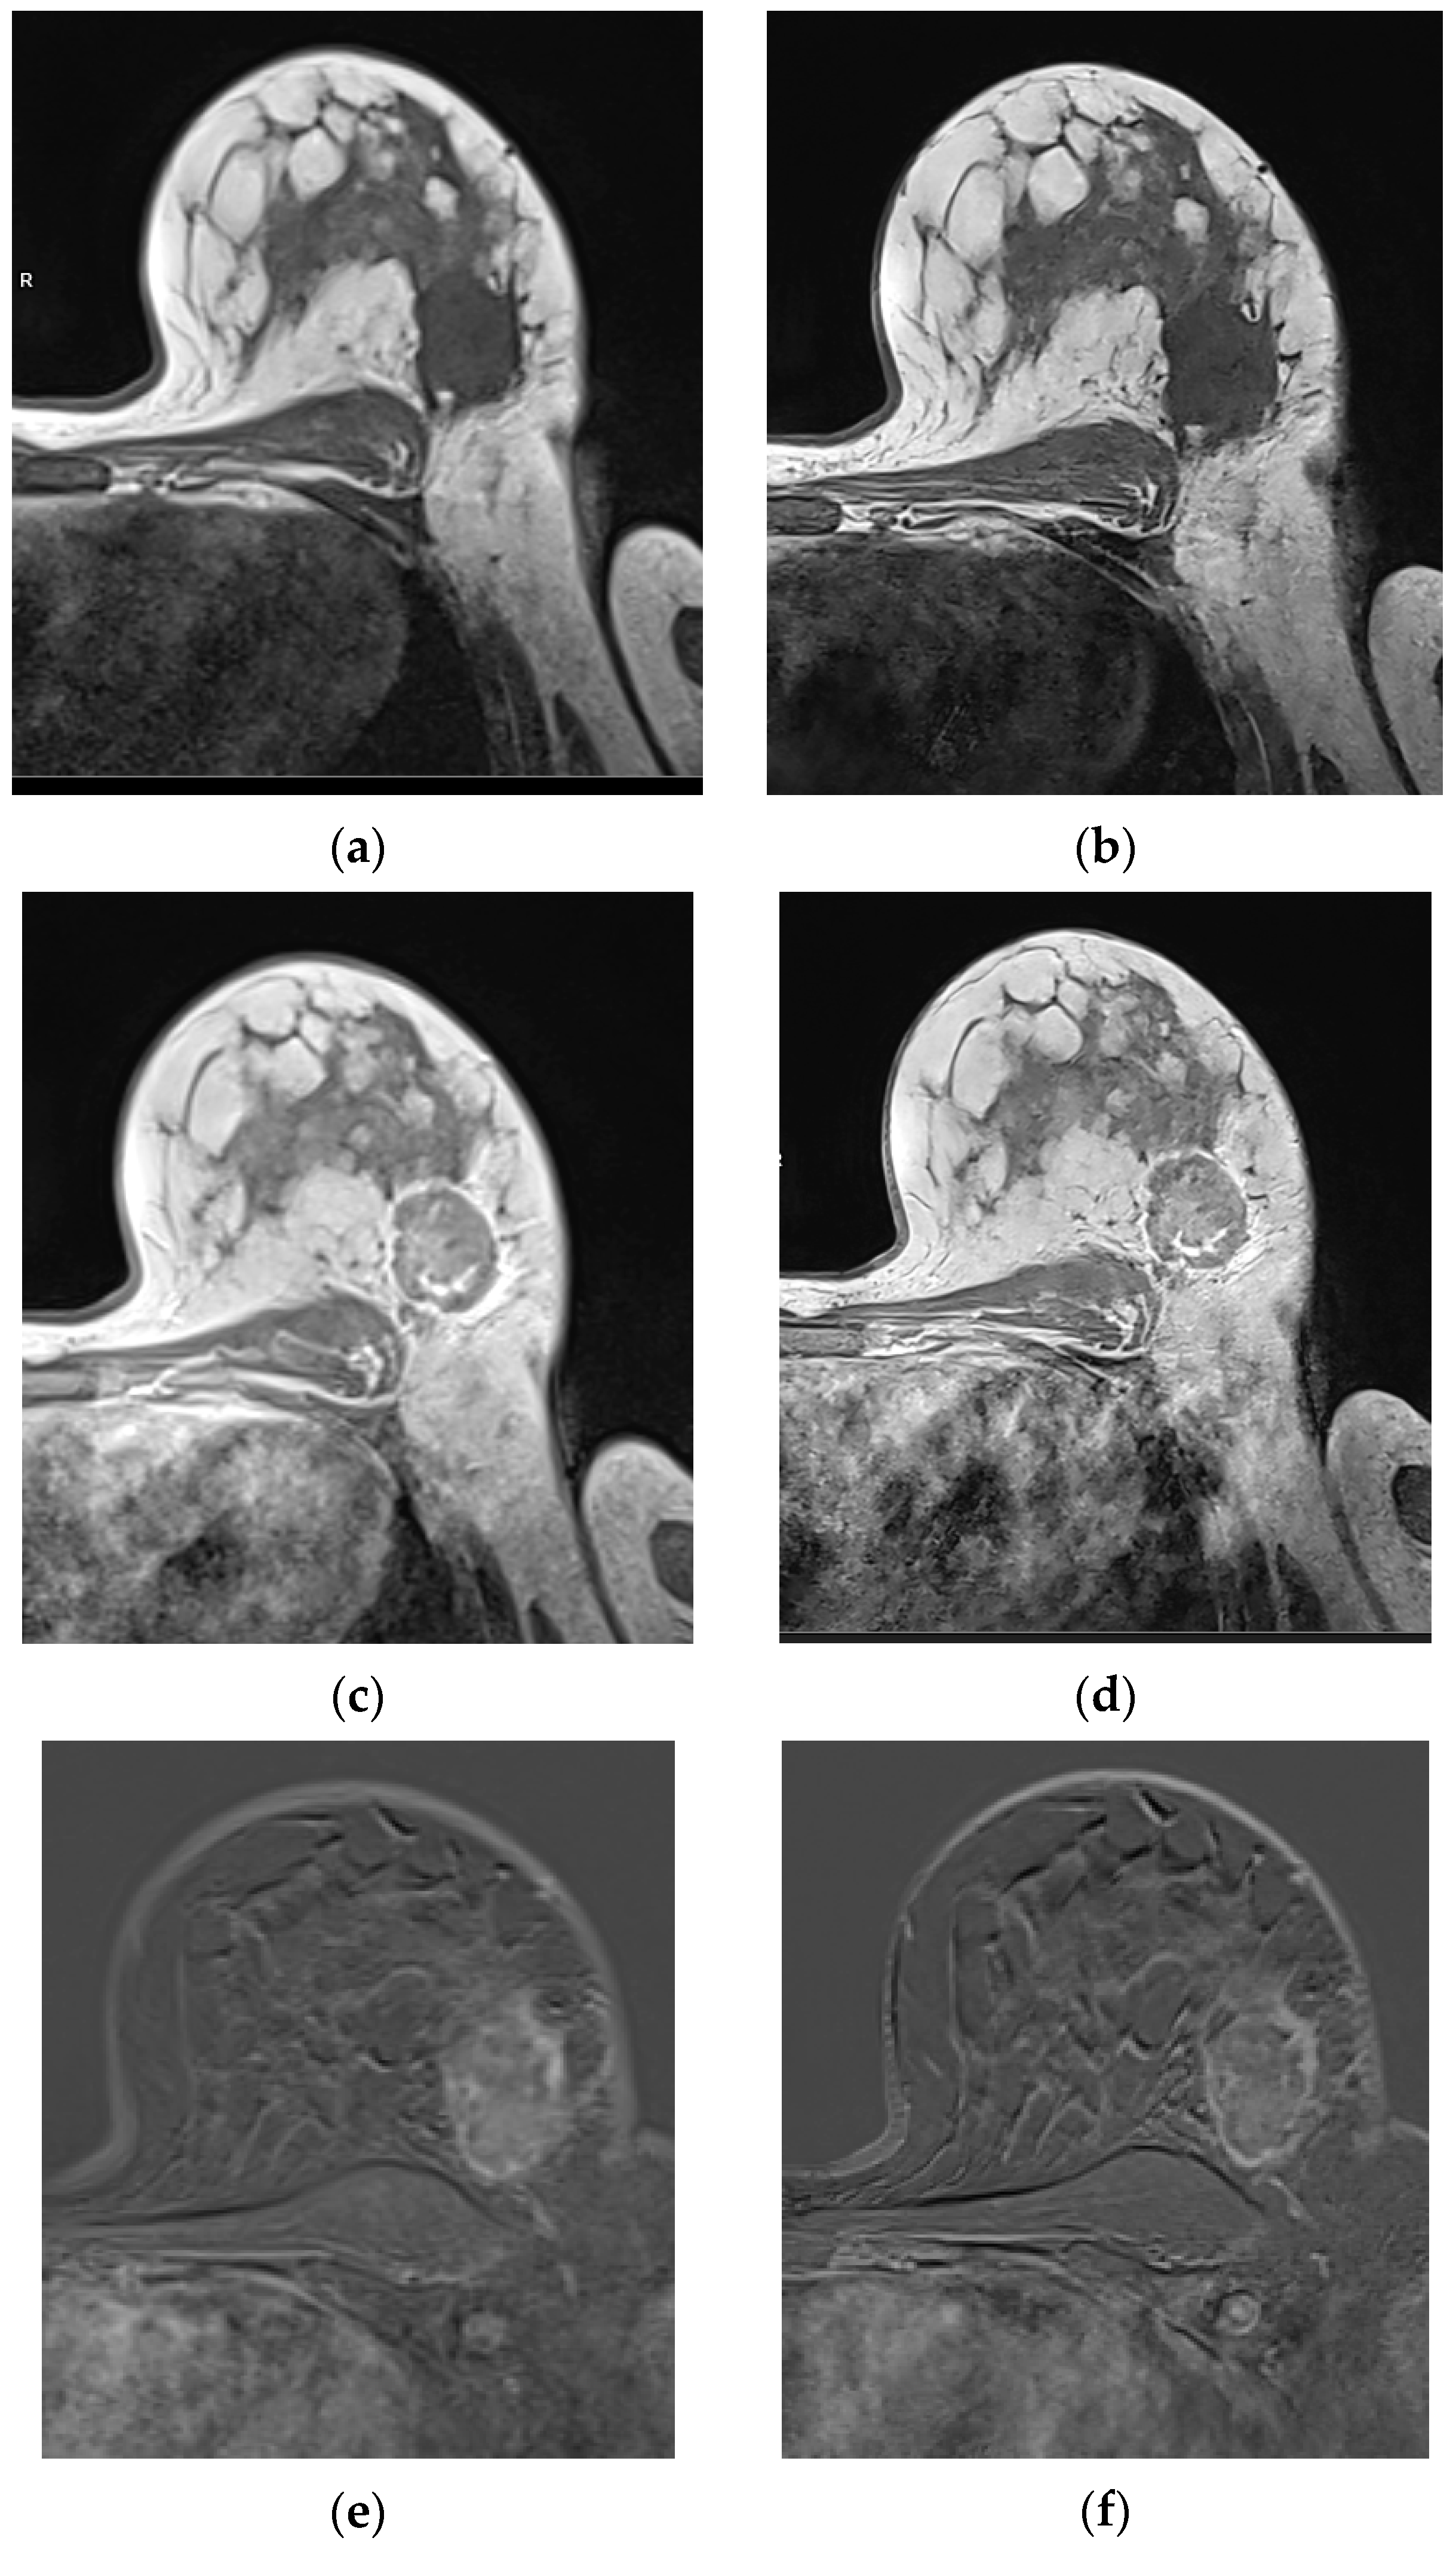

3.2.1. Qualitative Image Evaluation for T1w VIBE Pre-Contrast

3.2.2. Qualitative Image Evaluation for T1w VIBE Post-Contrast

3.3. Qualitative Image Evaluation for Post-Contrast Subtraction Images (SUB)